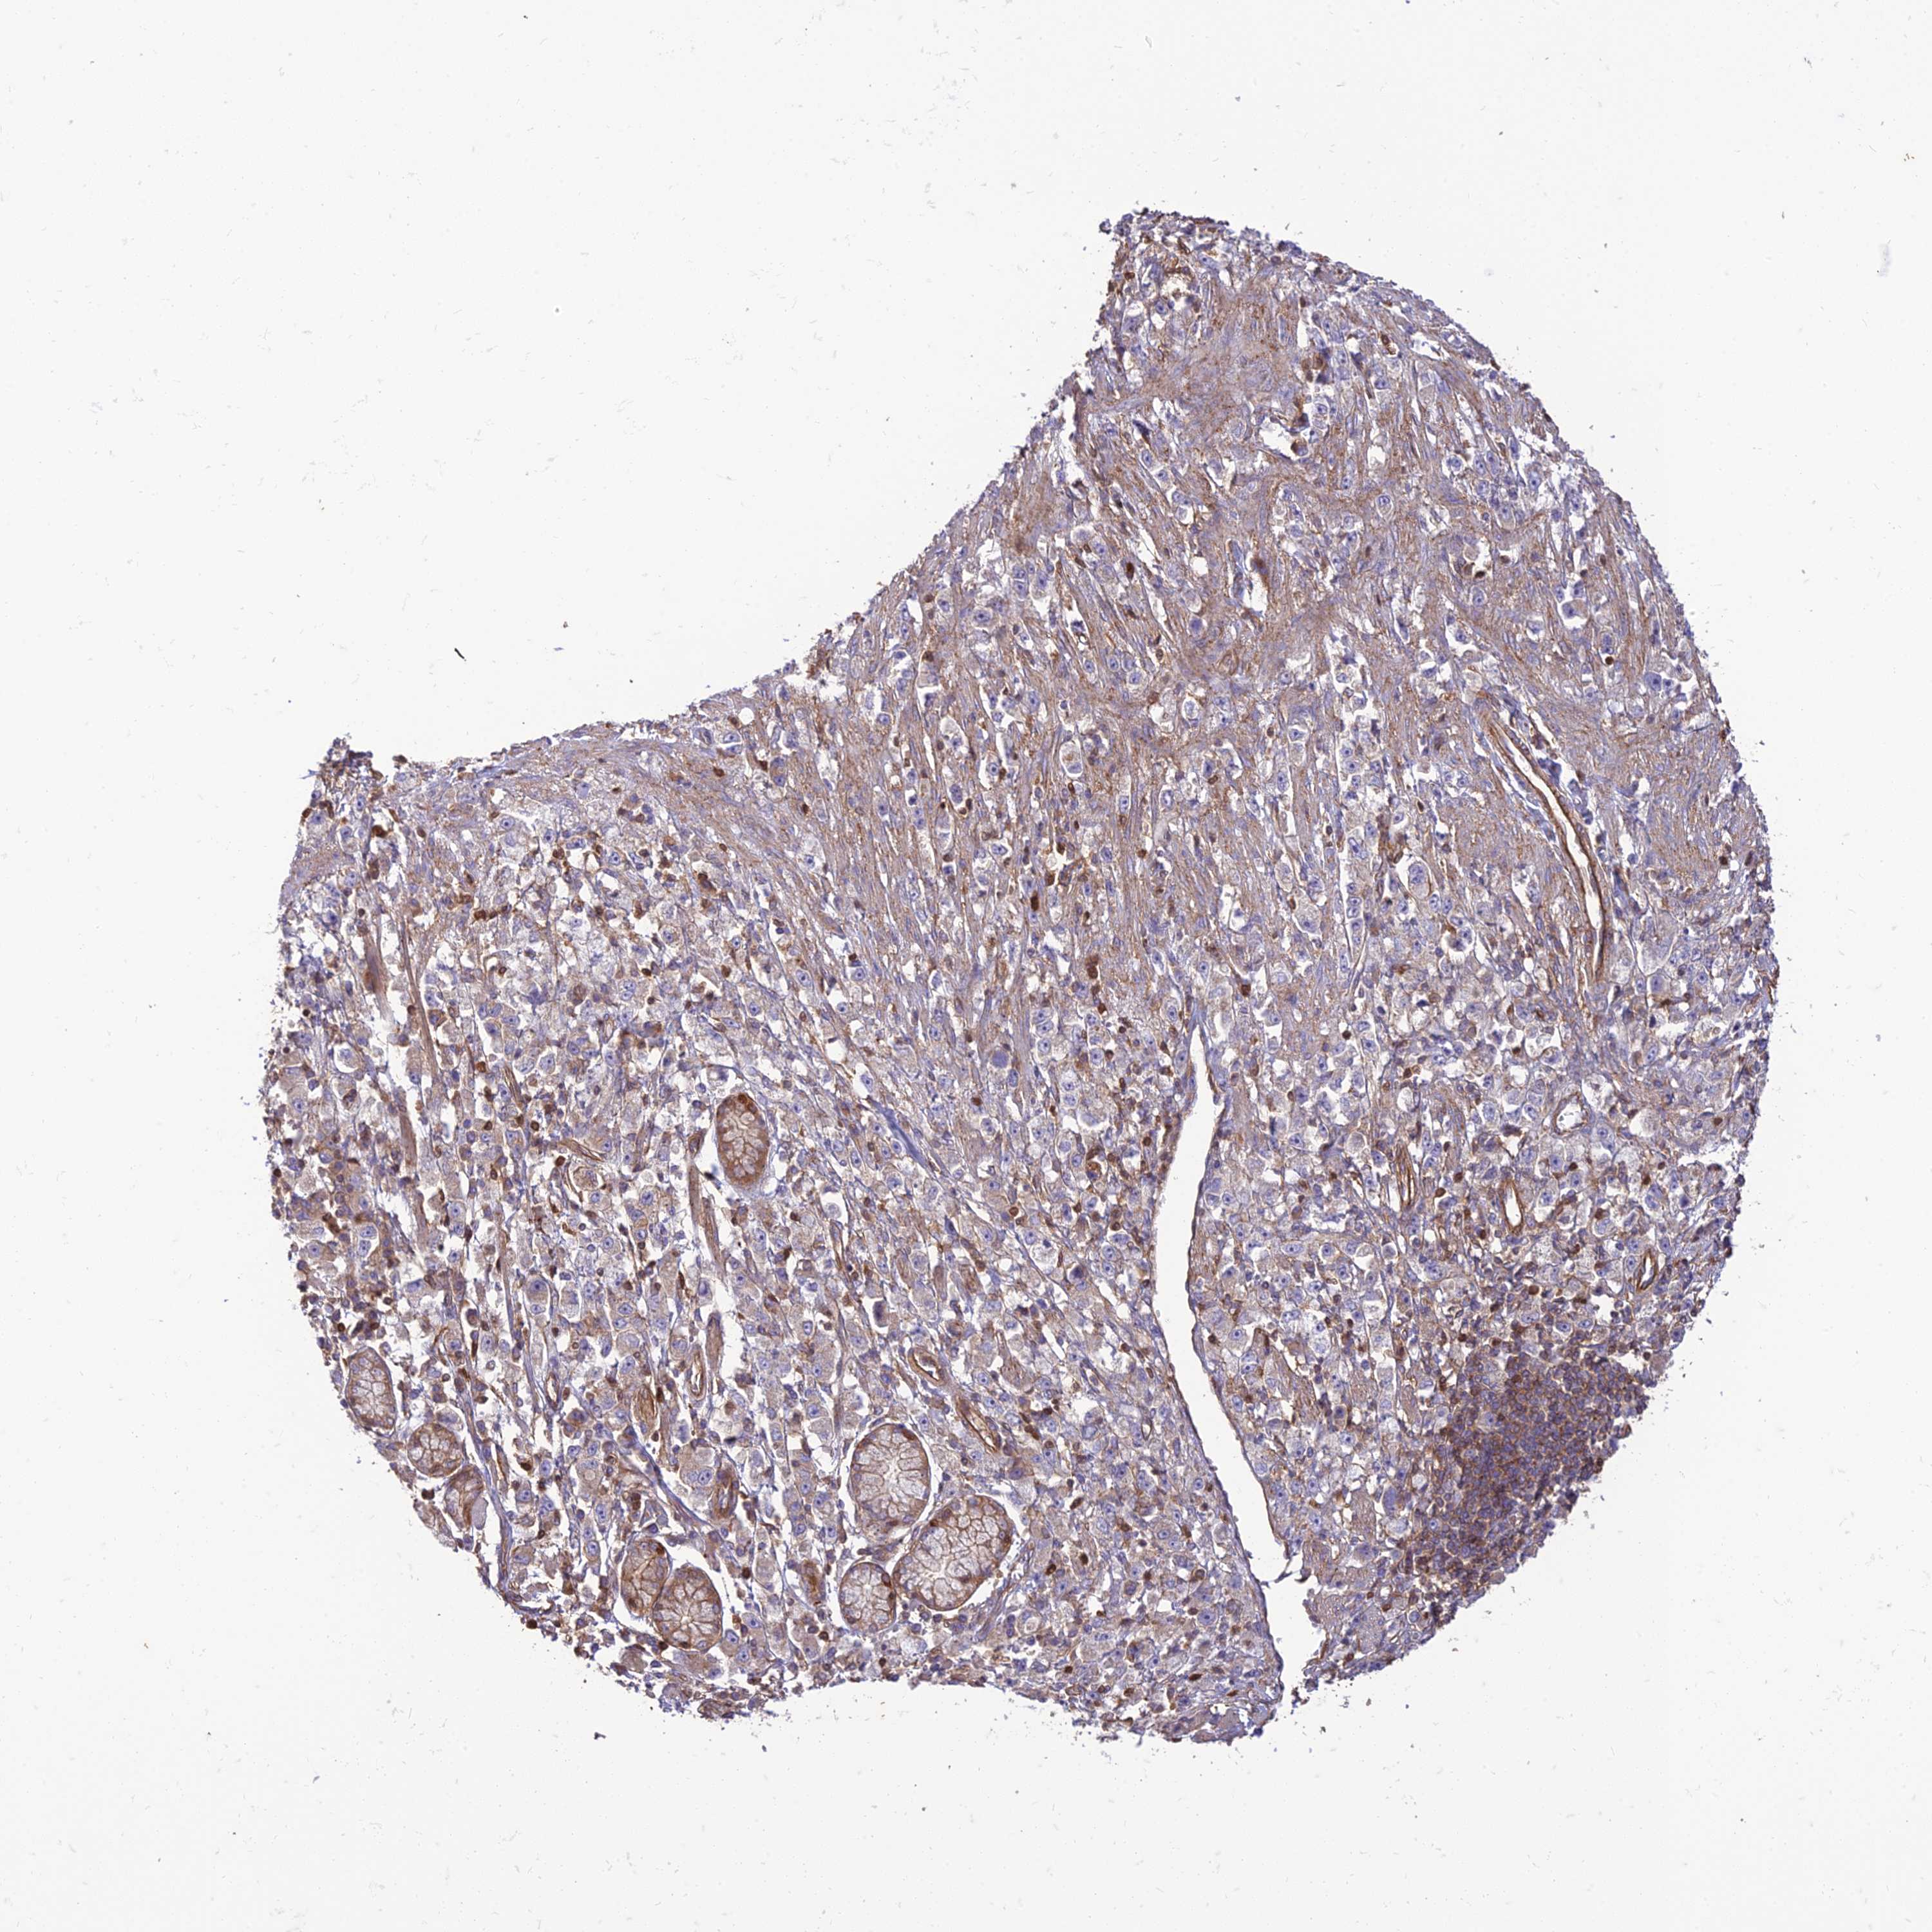

STOMACH CANCER - Protein expressioni

A mouse-over function shows sample information and annotation data. Click on an image to view it in a full screen mode. Samples can be filtered based on level of antibody staining by selecting one or several of the following categories: high, medium, low and not detected. The assay and annotation is described here.

Note that samples used for immunohistochemistry by the Human Protein Atlas do not correspond to samples in the TCGA dataset.

Antibody stainingi

Antibody staining in the annotated cell types in the current human tissue is reported as not detected, low, medium, or high, based on conventional immunohistochemistry profiling in selected tissues. This score is based on the combination of the staining intensity and fraction of stained cells.

Each image is clickable and will lead to virtual microscopy that enables deeper exploration of all samples and also displays staining intensity scores, fraction scores and subcellular localization as well as patient and tissue information for each sample.

Antibody HPA044603

Staining

High

Medium

Low

Not detected

Intensity

Strong

Moderate

Weak

Negative

Quantity

>75%

75%-25%

<25%

None

Location

Nuclear

Cytoplasmic/membranous

Cytoplasmic/membranous,nuclear

Adenocarcinoma, NOS